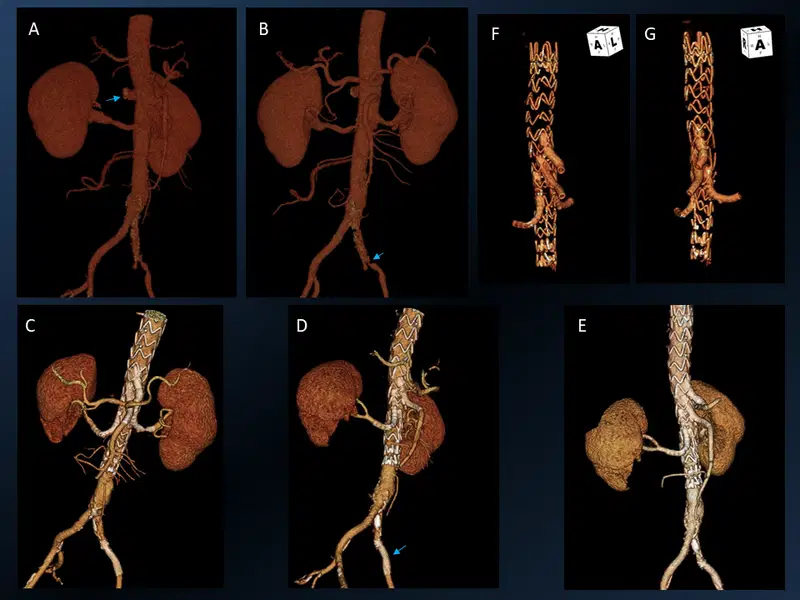

3. Mechanical Thrombectomy with aspiration only technique

Mechanical Thrombectomy with aspiration only technique CT, CT perfusion and angiogram images

Young patient with left sided dense hemiplegia while working out in gym. Time of onset 3 hrs. Plain CT demonstrates early changes of acute stroke in the right MCA territory (A). CTA confirms right M1 occlusion (B). Perfusion imaging (C) shows mismatch ratio of 7.9 with good volume of salvageable brain (green shade). DSA re-demonstrated the right M1 occlusion which was successfully removed using only suction, ADAPT resulting in TICI 3 outcome (E).